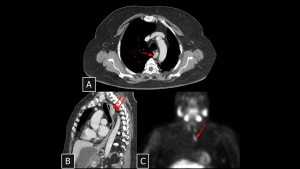

Fig 10: Case 11 – Paravertebral Paraganglioma:

Unenhanced CT (A) reveals a paravertebral mass extending from the retroperitoneum into the thorax. The intense arterial enhancement seen in Panel B is the key diagnostic feature, confirming the tumor's hypervascular nature and distinguishing it from other neurogenic lesions.

SYSTEMATIC APPROACH: 1. Age: Adults (40–50 years; younger in hereditary cases). | 2. Morphology: Highly vascular soft-tissue mass ("Salt-and-pepper" on MRI). | 3. Enhancement: Intense/Avid arterial enhancement. | 4. Relevant Anatomical Relationships: Paravertebral (Sympathetic chain); intense uptake on DOTATATE/MIBG.

Fig 11: Case 12 – Castleman Disease:

Axial CT (A) reveals a right hilar mass with extension to the ipsilateral posterior mediastinum. Coronal view (B) demonstrates the anatomical relationship with the bronchi. The lesion showed uptake on 18 FDG PET CT (C) but remained stable over a 3-year period, consistent with this benign lymphoproliferative disorder.

SYSTEMATIC APPROACH: 1. Age: Young Adults / Adults. | 2. Morphology: Solitary, non-necrotic mass. | 3. Enhancement: Intense homogeneous enhancement (mimicking paraganglioma). | 4. Relevant Anatomical Relationships: Unicentric distribution; often visceral or vascular interface.